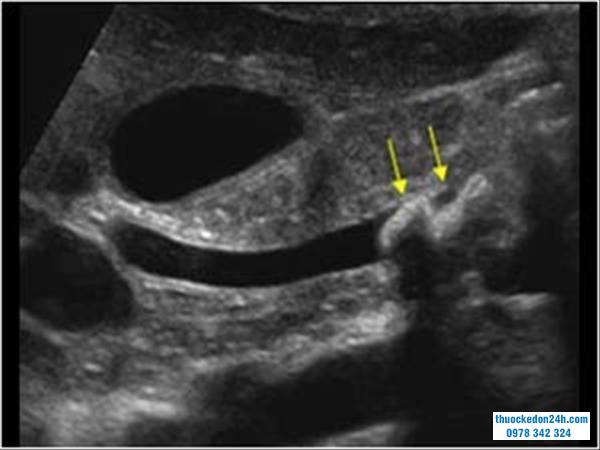

Xác định được vị trí và kích thước của sỏ mật chủ trên siêu âm với kết quả chuẩn xác đến 95%.Siêu âm được tiến hành trên phạm vi rộng rãi để hỗ trợ chẩn đoán cho các bệnh lý gan mật.Hình ảnh sỏi mật trên siêu âm thường là cấu trúc tang âm kèm bóng cản và nằm trong ống mật chủ. Tương tự, sỏi túi mật sẽ thấy bóng cản đậm nằm trong túi mật.

Hình ảnh sỏi ống mật chủ trên siêu âm